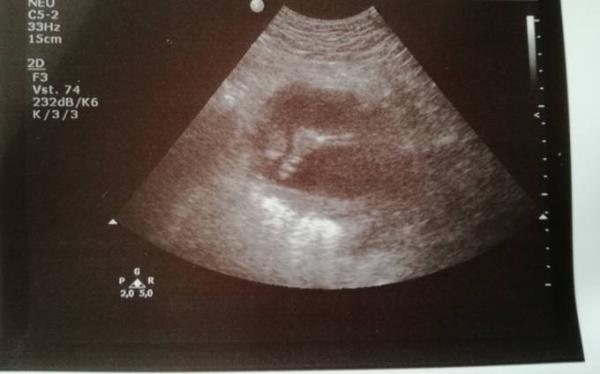

Wie immer höchst aktiv und kaum einzufangen. Herzchen und Organe laut Arzt alles super, 20 cm groß und zeitgerecht entwickelt.

Als es zum Geschlecht ging, tadaaa Nabelschnur zwischen den Beinen. Beim letzten Mal vor 4 Wochen hatte er noch die Vermutung es könnte ein Bub werden weil ein Schatten zwischen den Beinen zu sehen war, diesmal sah er aber nur eine Nabelschnur klar darstellbar, aber nichts weiteres. Er sagte mittlerweile müsste man etwas sehen falls es ein Bub wird, also Tendenz zum Mädchen, ich hoffe es sehr aber glauben kann ich noch nicht so wirklich daran, auch wenn ich von Anfang an sage das es ein Mädchen wird.

Als Foto bekam ich kleine Füße die sie uns präsentierte.